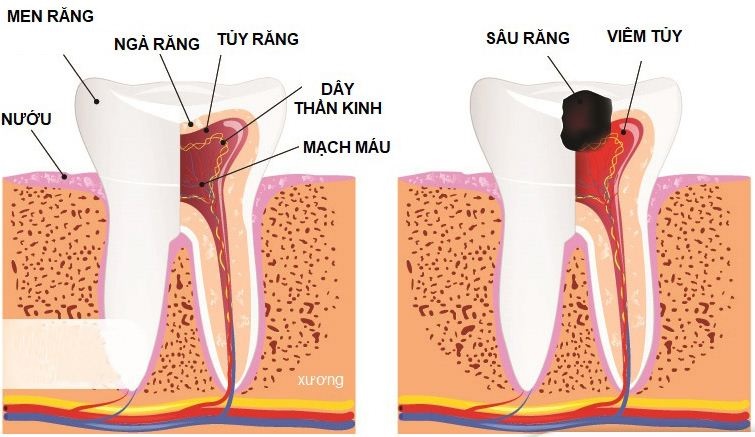

Nguyên nhân gây viêm tủy răng phổ biến nhất

1. Sâu răng nặng

Đây là nguyên nhân hàng đầu gây viêm tủy răng. Khi sâu răng không được điều trị sớm, vi khuẩn sẽ ăn mòn men răng và ngà răng, sau đó xâm nhập vào tủy gây viêm nhiễm.